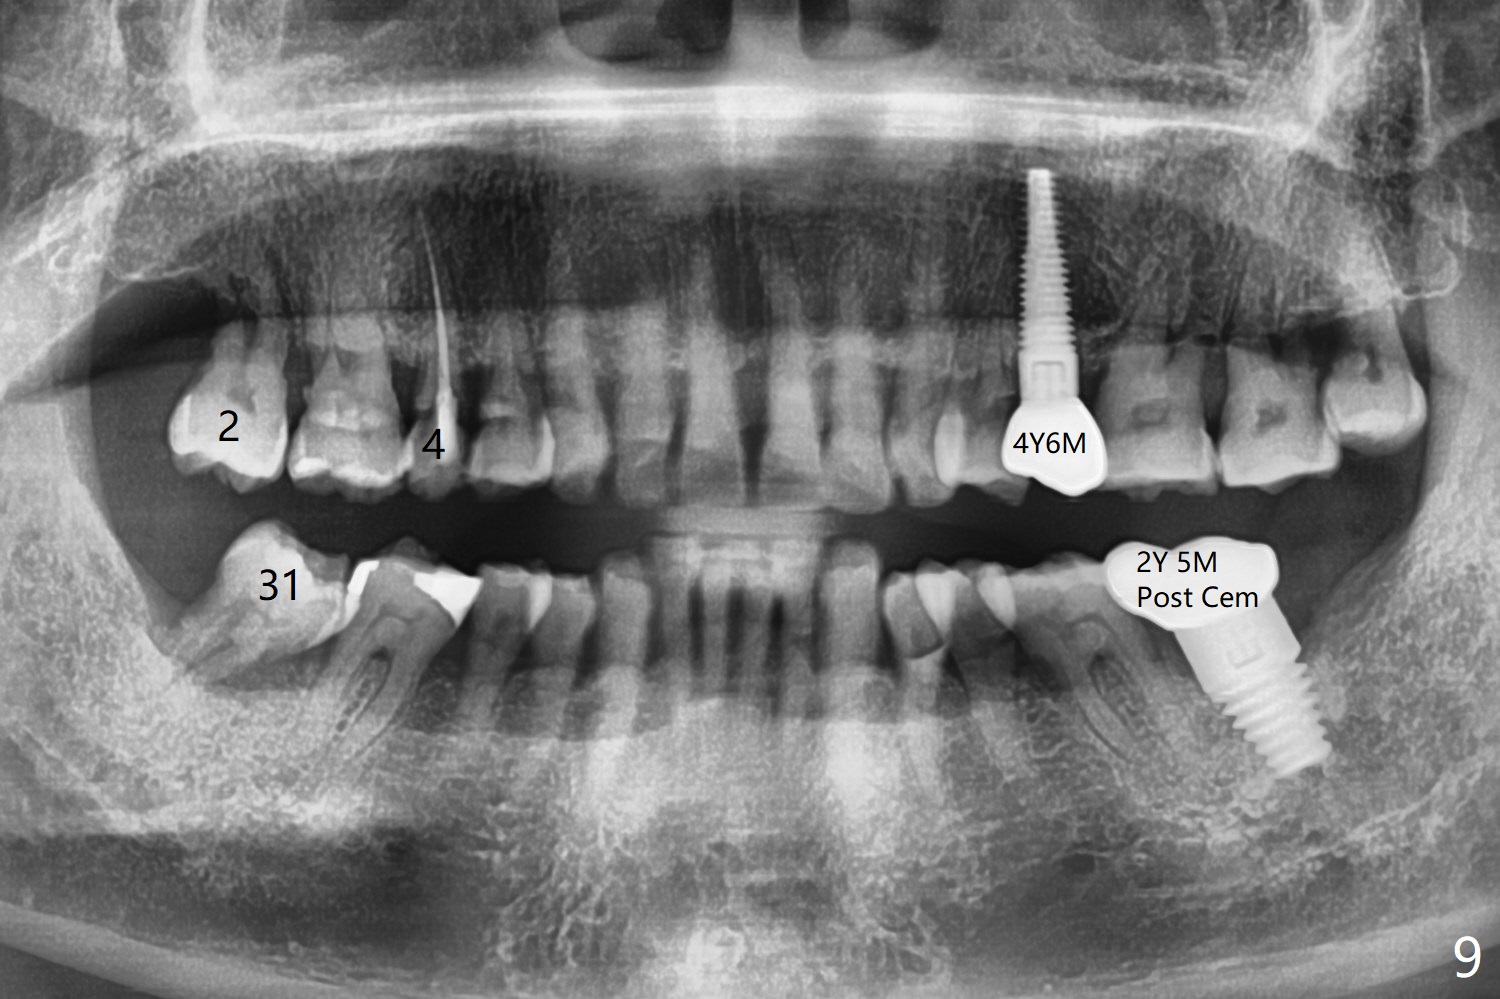

It appears that the patient chews on the left postop, since the provisional perforates with loose abutment nearly 3 months postop and the tooth #3 has occlusal sensitive chip. The implants seems to have osteointegrated (Fig.6). To improve oral hygiene, the provisional is not recemented. The patient will return for impression in 2 weeks. It appears that there is short healing time for large implant. There is no bone loss 7 months post cementation (Fig.7). The buccal gingiva is lightly erythematous without tenderness 1 year 7.5 months post cementaion. Water pik is being used, although chronic periodontitis is not under control. Retrospectively, surgery should be shifted to socket preservation when a moderate implant (5 or 5.5 mm) fails to achieve primary stability. The extra large implant (8 mm for example) leaves a little gap buccolingually. Guided surgery would allow precise placement of the moderate implant without change in trajectory. The crown becomes loose because of occlusal perforation and limited vertical space. When a new crown is cemented, the bone density around the coronal threads is high (Fig.8 *). While the bone remains stable at #4 (6 months post RCT), 13 (4 years 6 months post cementation) and 18 (2 years 5 months post cementation), there is severe bone loss at #2 and 31 (Fig.9).